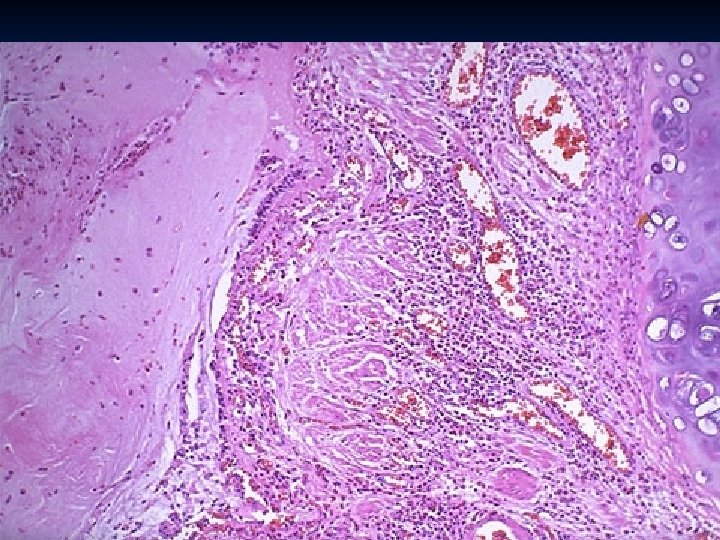

Bronchiectasis - Permanent abnormal dilation of bronchi and bronchioles, - Usually associated with chronic necrotizing inflammation - Patients have fever, cough, foul–smelling sputum. - More common in left lung, lower lobes.

Causes: n Obstruction (tumor, mucus) n Congenital n Intralobar sequestration n Cystic fibrosis n Immotile cilia syndrome n Necrotizing pneumonia n Kartaganer’s Syndrome